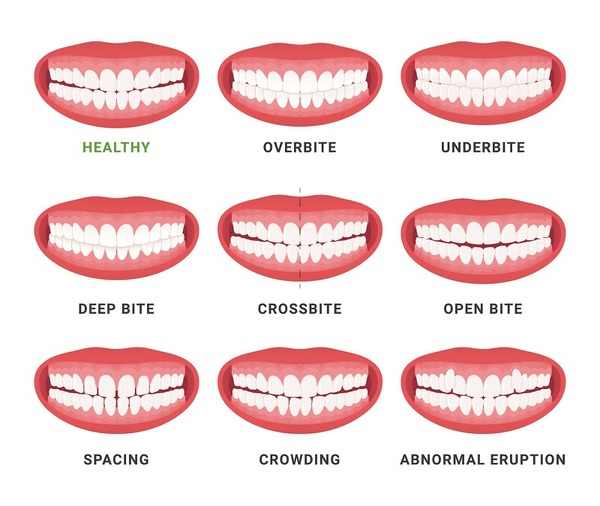

chun liên hàm sẽ phát huy hiệu quả tối đa với những trường hợp đặc biệt sau:

- Khớp cắn hở hoặc khớp lệnh.

- Tỷ lệ xô lệch răng lớn.

- Trường hợp răng khểnh ở mức độ nặng.

Thun liên hàm có vai trò quan trọng trong việc điều chỉnh khoảng cách giữa các răng, kiểm soát hướng phát triển của răng và cải thiện chức năng khớp cắn. Dưới đây là những trường hợp phù hợp để sử dụng thun liên hàm:

- Răng hô (Hàm trên nhô ra quá mức): Khi răng hàm trên chìa ra nhiều hơn so với hàm dưới, việc sử dụng thun liên hàm giúp kéo hàm trên vào trong và đẩy hàm dưới ra ngoài, giúp cân bằng khớp cắn.

- Hàm móm (Hàm dưới nhô ra quá mức): Nếu răng hàm dưới phát triển quá mức về phía trước so với răng hàm trên, thun liên hàm sẽ hỗ trợ kéo hàm trên ra ngoài và điều chỉnh vị trí hàm dưới về sau, giúp cải thiện tình trạng lệch khớp cắn.

- Khớp cắn hở: Đây là tình trạng mà răng hàm trên và hàm dưới không tiếp xúc được với nhau khi cắn lại. Sử dụng thun liên hàm giúp điều chỉnh các răng về đúng vị trí, tạo sự tiếp xúc giữa hai hàm để cải thiện chức năng nhai.